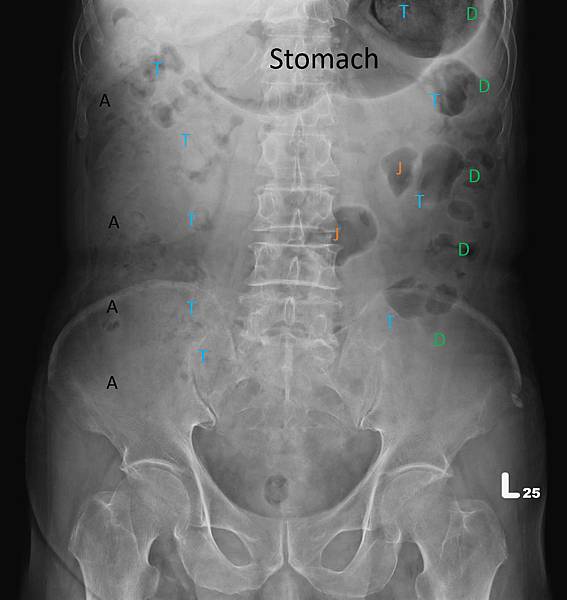

KUB看不出她的病有多嚴重:

WBC 13600/ul, Seg 93.4%

CRP 48.7 mg/dL

看到這些抽血數值,大家都會猜急性闌尾炎。